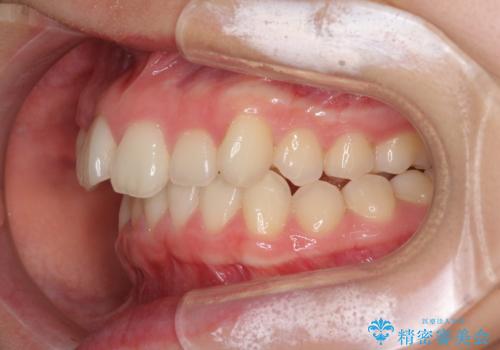

- 上顎前歯のデコボコを気にして来院された患者様です。

口元の突出感はなく、上顎のみに顕著な叢生が認められました。

上顎の左右第一小臼歯2本を抜歯し、ワイヤー装置にて歯列を整えることとしました。